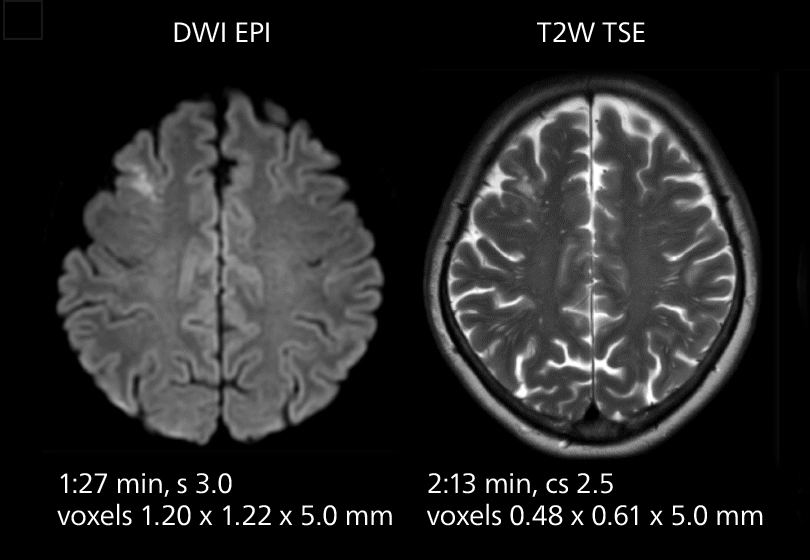

Brain MRI

These images of an old cerebral infarction demonstrate the speed and image quality after upgrading to Elition X.